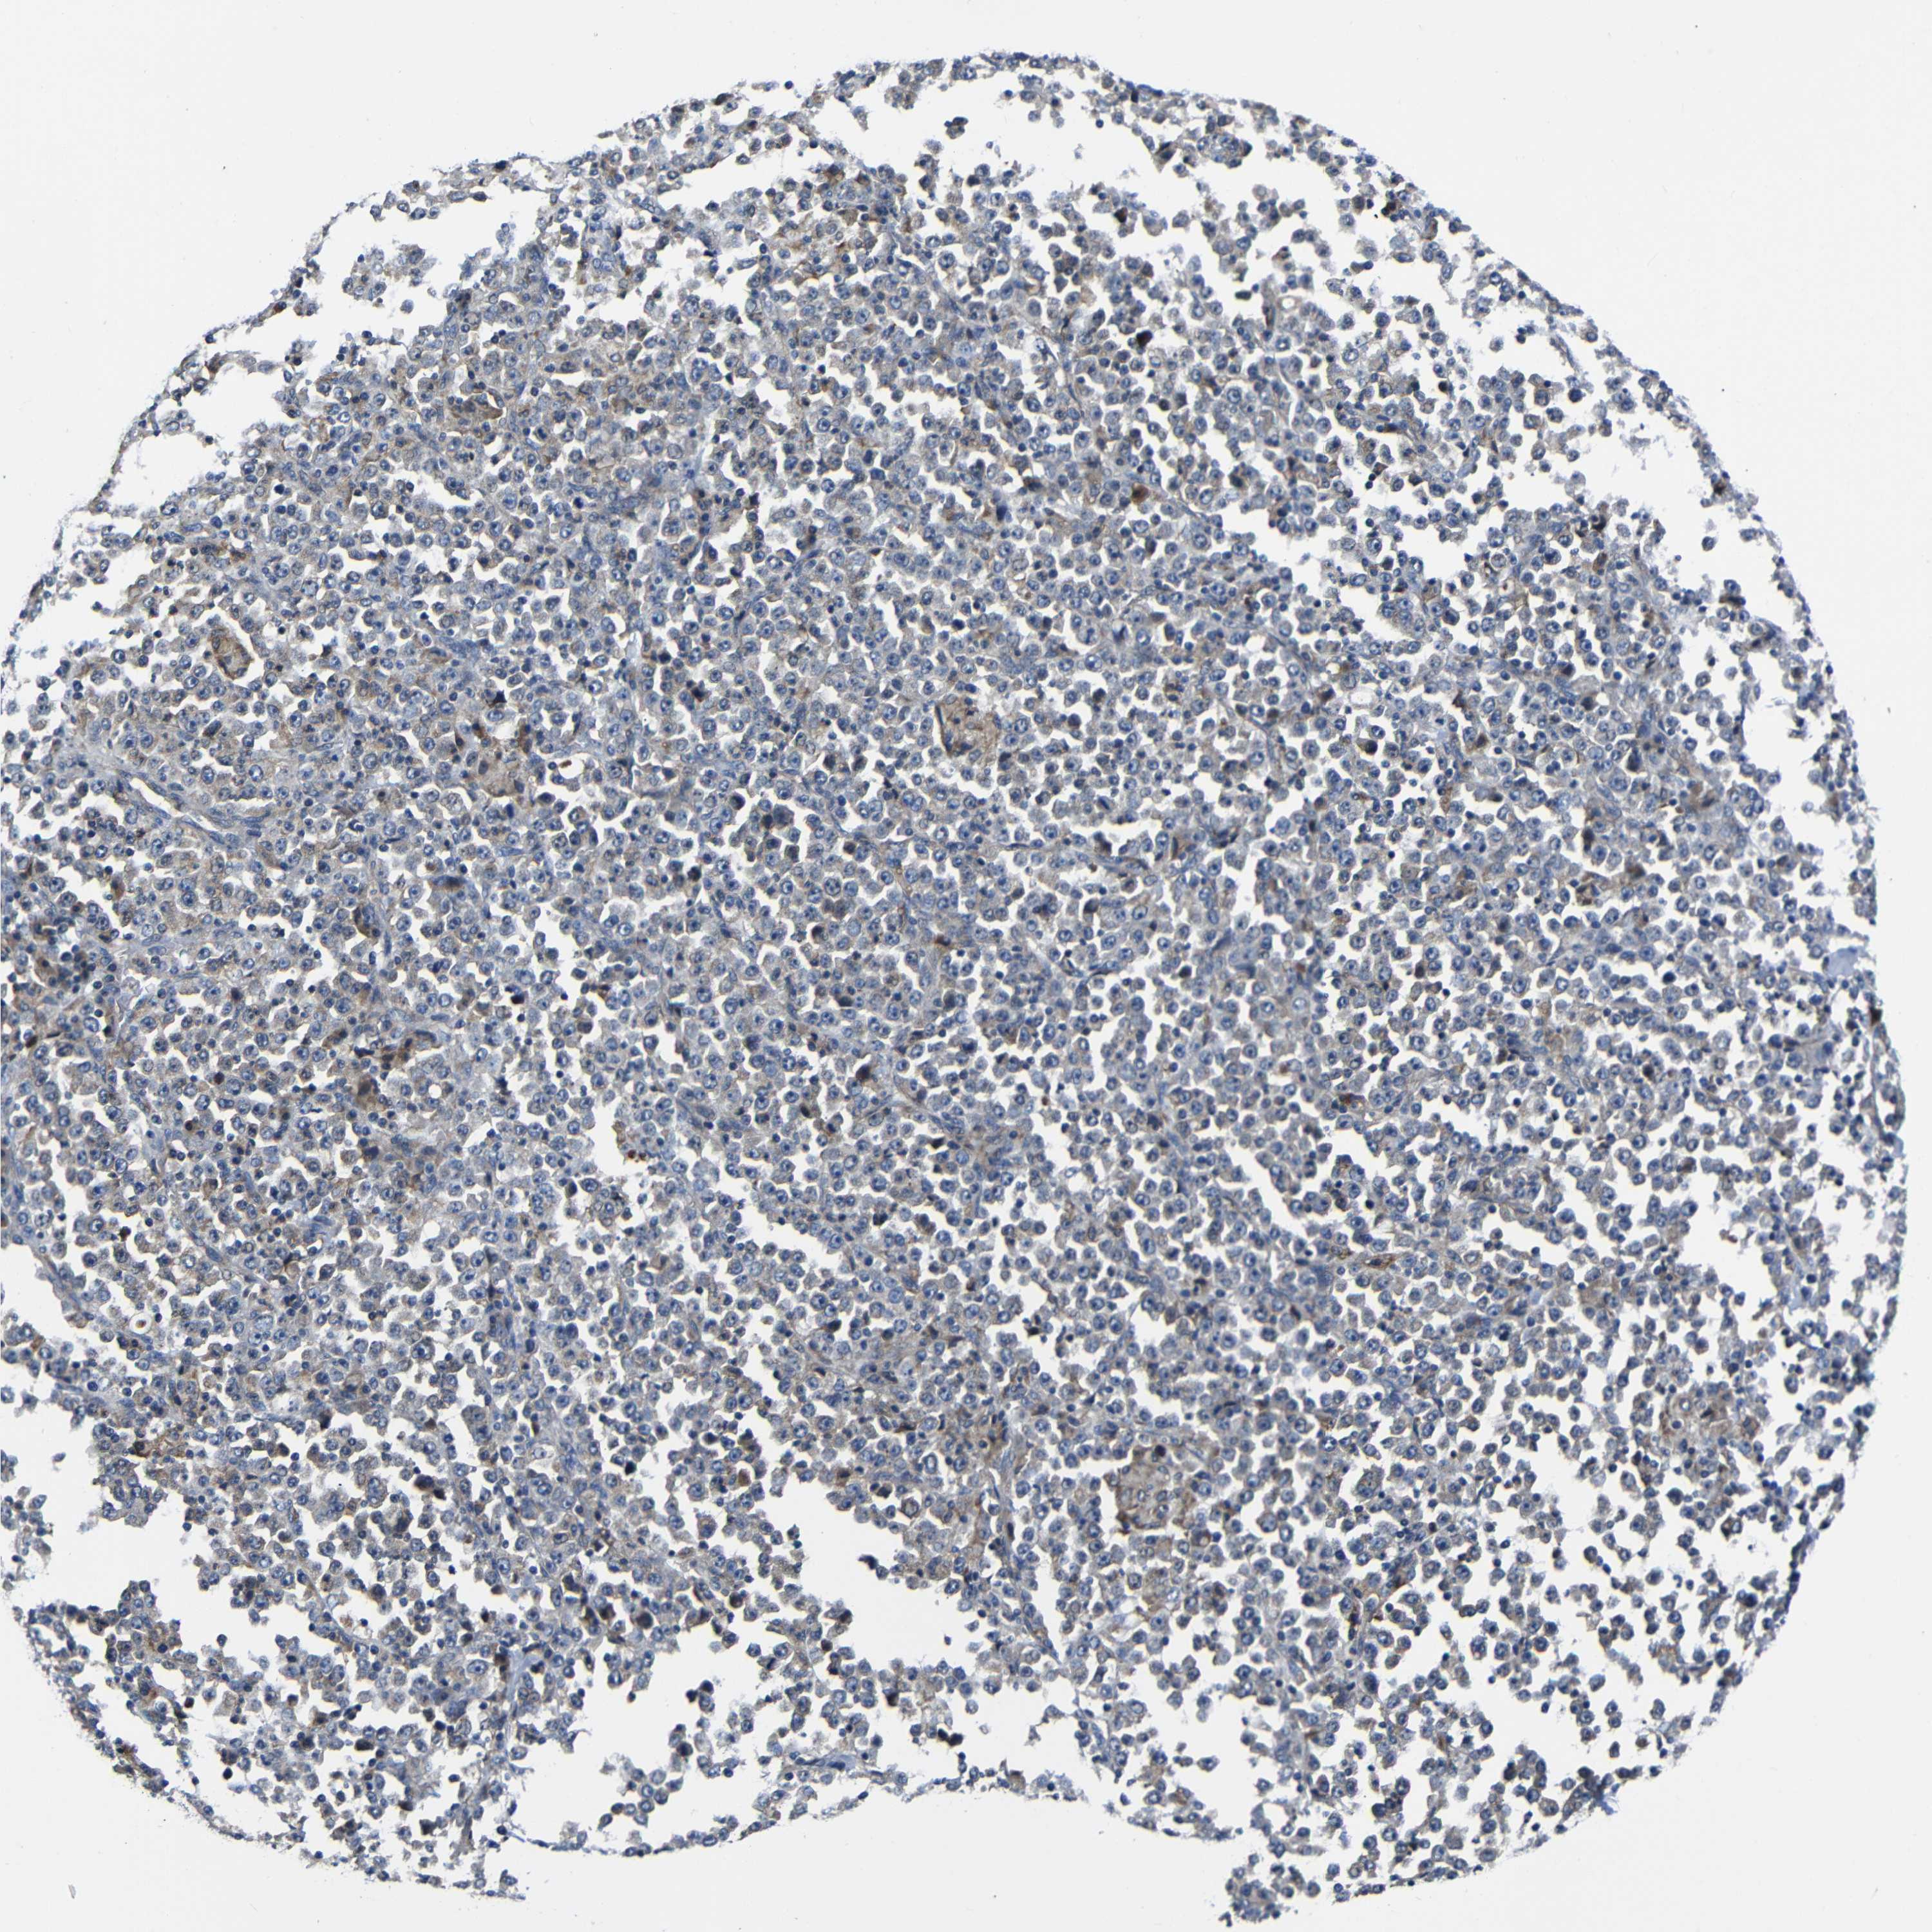

STOMACH CANCER - Protein expressioni

A mouse-over function shows sample information and annotation data. Click on an image to view it in a full screen mode. Samples can be filtered based on level of antibody staining by selecting one or several of the following categories: high, medium, low and not detected. The assay and annotation is described here.

Note that samples used for immunohistochemistry by the Human Protein Atlas do not correspond to samples in the TCGA dataset.

Antibody stainingi

Antibody staining in the annotated cell types in the current human tissue is reported as not detected, low, medium, or high, based on conventional immunohistochemistry profiling in selected tissues. This score is based on the combination of the staining intensity and fraction of stained cells.

Each image is clickable and will lead to virtual microscopy that enables deeper exploration of all samples and also displays staining intensity scores, fraction scores and subcellular localization as well as patient and tissue information for each sample.

HPA030212

HPA030213

HPA030214

HPA030215

CAB013496

Adenocarcinoma, NOS